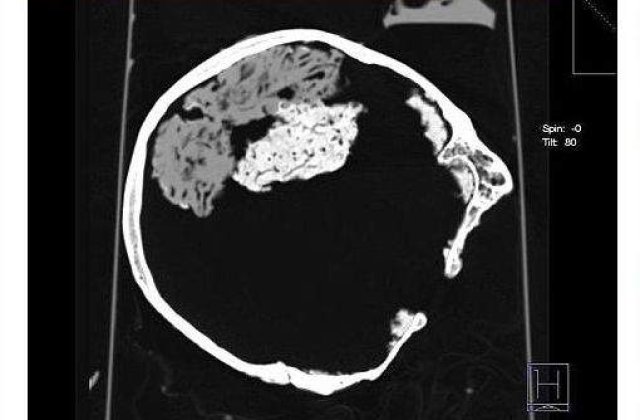

Testele au arata ca tesutul cerebral apartine unui barbat care a trait acum 2.500 de ani si care a fost sacrificat intr-un ritual sadic in Epoca Fierului.

“Gasirea unui tesut cerebral, atunci cand niciun altfel de tesut nu mai exista pe schelet este un eveniment foarte rar. Creierul s-a pastrat intr-o forma foarte buna, desi, in mod normal, tesutul cerebral dispare in cativa ani dupa moarte”, a declarat cercetatoarea Sonia O'Connor de la Universitatea din Bradford pentru Daily Mail.

Acum cercetatorii incearca sa determine care au fost conditiile in care creierul s-a pastrat intact, in ciuda factorilor biologici care ar fi trebuit sa il elimine din craniu, in urma cu multi ani.